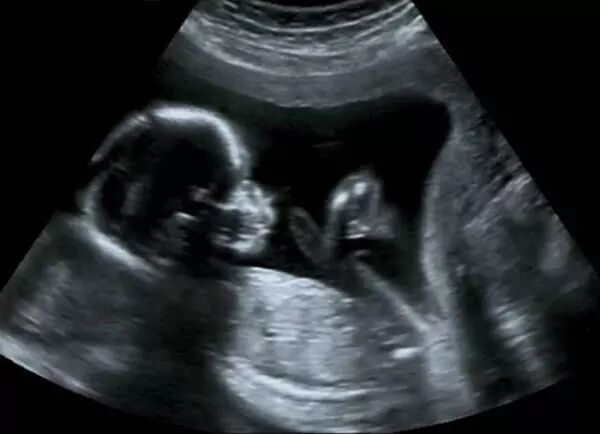

如此,乘兴而来败兴而归,反反复复四五趟之后,医生也烦了,结果四维彩超拍得没个任性

眼睛、鼻子、嘴巴~这~这~,亲爱的宝贝,妈妈一样也找不到啊!!